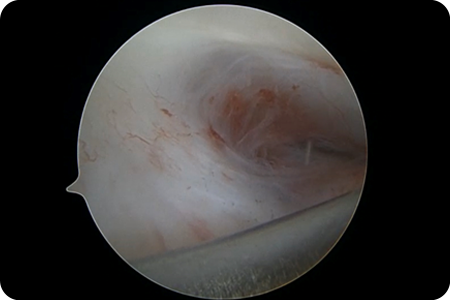

- Arthroscopy